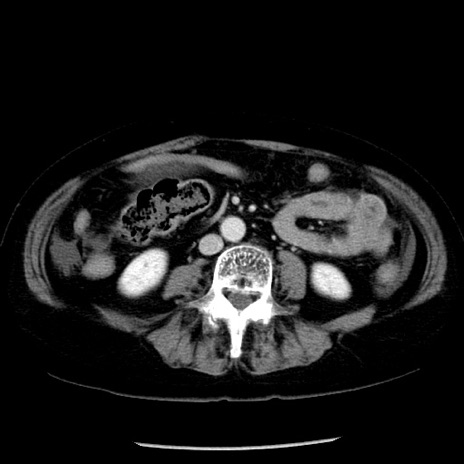

症例13(横断像)

【症例】70歳代女性

【主訴】腹痛、嘔吐

【現病歴】15時間程前(昨晩)より腹痛あり。今朝になっても症状の改善なく、嘔吐あり。腹痛も増悪あり、救急外来受診。

【既往歴】子宮癌全摘術後

【身体所見】意識清明、BP 121/72mmHg、P 74bpm、SpO2 100%(RA)、腹部:平坦・軟、腸雑音ほぼ聴取せず。下腹部・心窩部・臍左上に圧痛あり。反跳痛なし。

【データ】WBC 10600、CRP 0.15